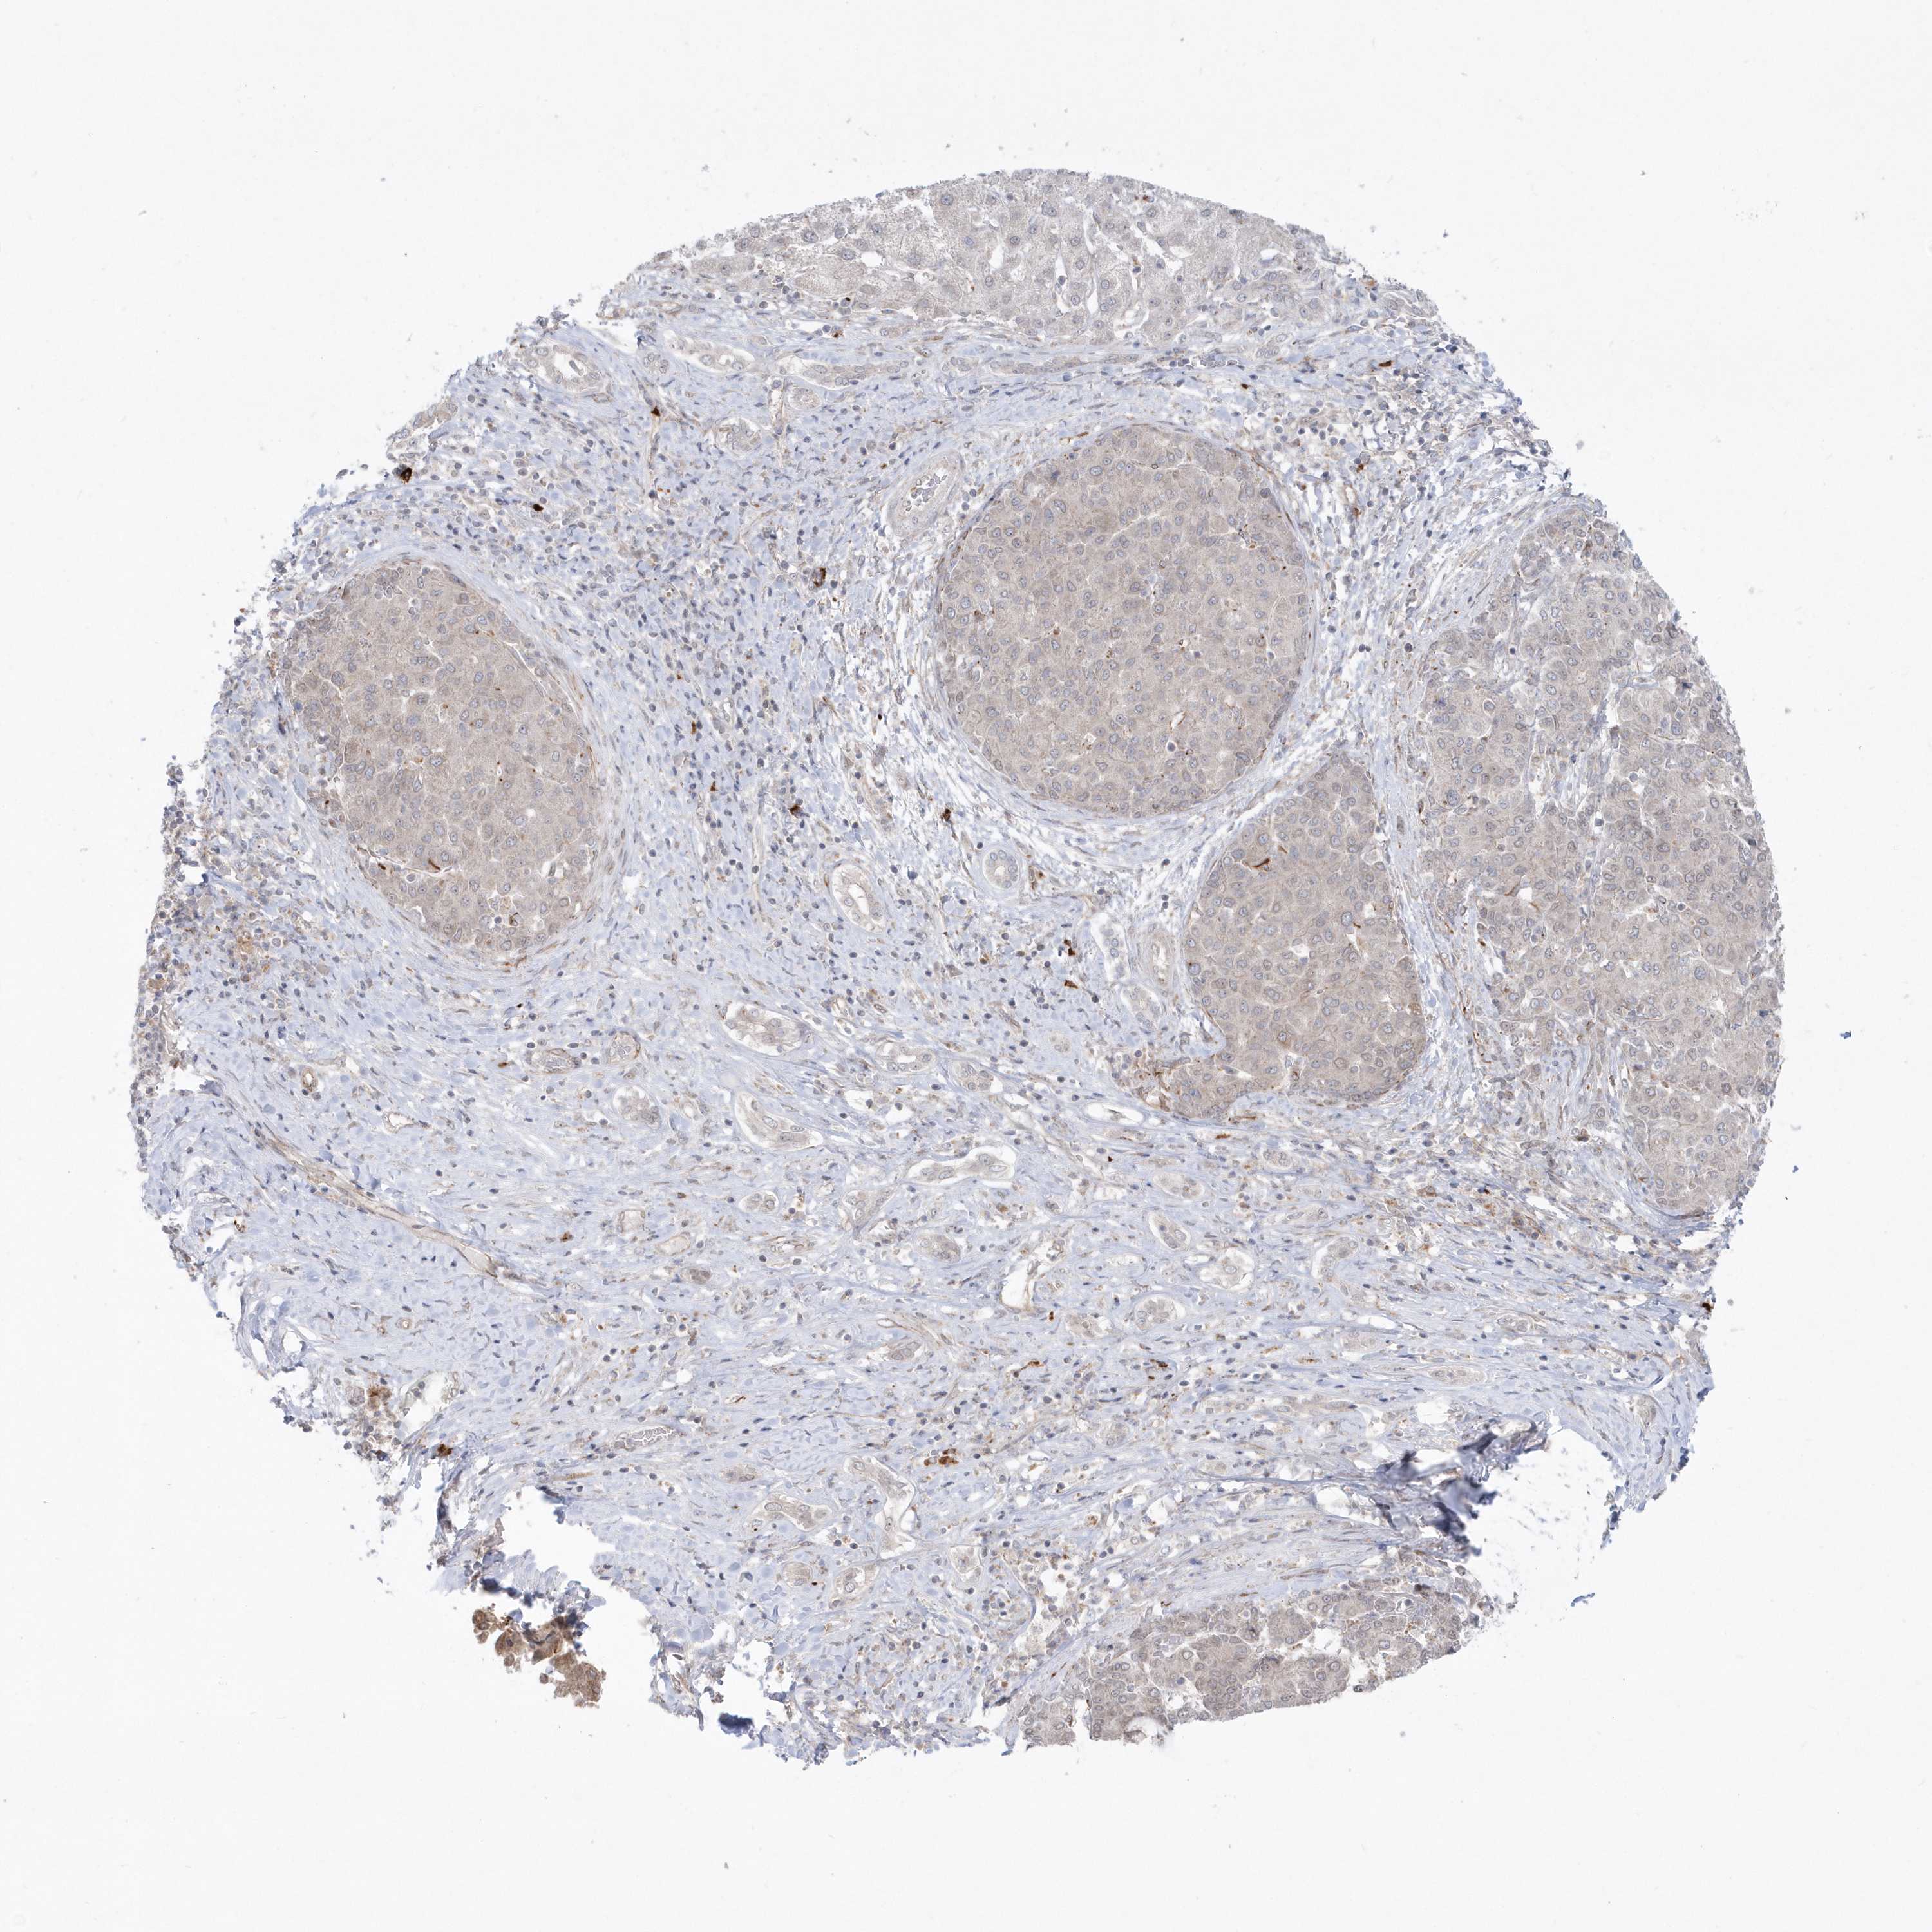

LIVER CANCER - Protein expressioni

A mouse-over function shows sample information and annotation data. Click on an image to view it in a full screen mode. Samples can be filtered based on level of antibody staining by selecting one or several of the following categories: high, medium, low and not detected. The assay and annotation is described here.

Note that samples used for immunohistochemistry by the Human Protein Atlas do not correspond to samples in the TCGA dataset.

Antibody stainingi

Antibody staining in the annotated cell types in the current human tissue is reported as not detected, low, medium, or high, based on conventional immunohistochemistry profiling in selected tissues. This score is based on the combination of the staining intensity and fraction of stained cells.

Each image is clickable and will lead to virtual microscopy that enables deeper exploration of all samples and also displays staining intensity scores, fraction scores and subcellular localization as well as patient and tissue information for each sample.

Antibody HPA036160

Staining

High

Medium

Low

Not detected

Intensity

Strong

Moderate

Weak

Negative

Quantity

>75%

75%-25%

<25%

None

Location

Nuclear

Cytoplasmic/membranous

Cytoplasmic/membranous,nuclear

Cholangiocarcinoma

Carcinoma, Hepatocellular, NOS